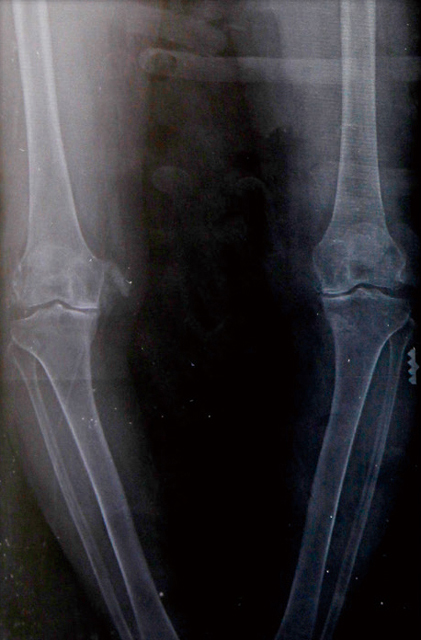

O脚のレントゲン

中高年の膝の痛みの原因で最も多いのが変形性膝関節症。加齢や使い過ぎなど膝に負担をかけ過ぎてきたために、膝の軟骨がすり減り、骨と骨とがぶつかって出てくる痛みです。女性に多いのも特徴で、40歳以上の膝をレントゲンで撮ると、女性の約6割には膝関節の変形がみられるといわれています。

膝の内側から悪くなることが多く、そのためO脚になりやすく、O脚になると体重が内側にかかり骨が削れ、さらに関節の変形が進むという悪循環をおこすことがあります。